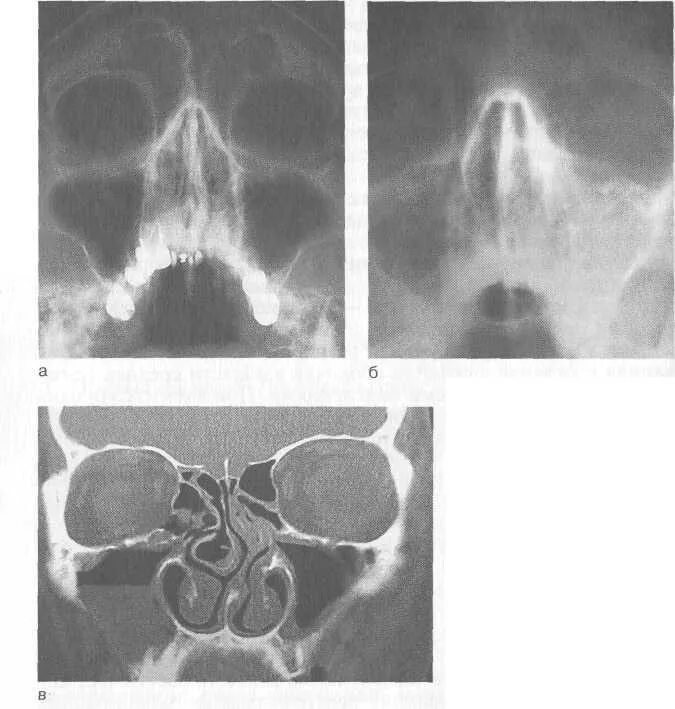

Отек слизистой оболочки верхнечелюстных